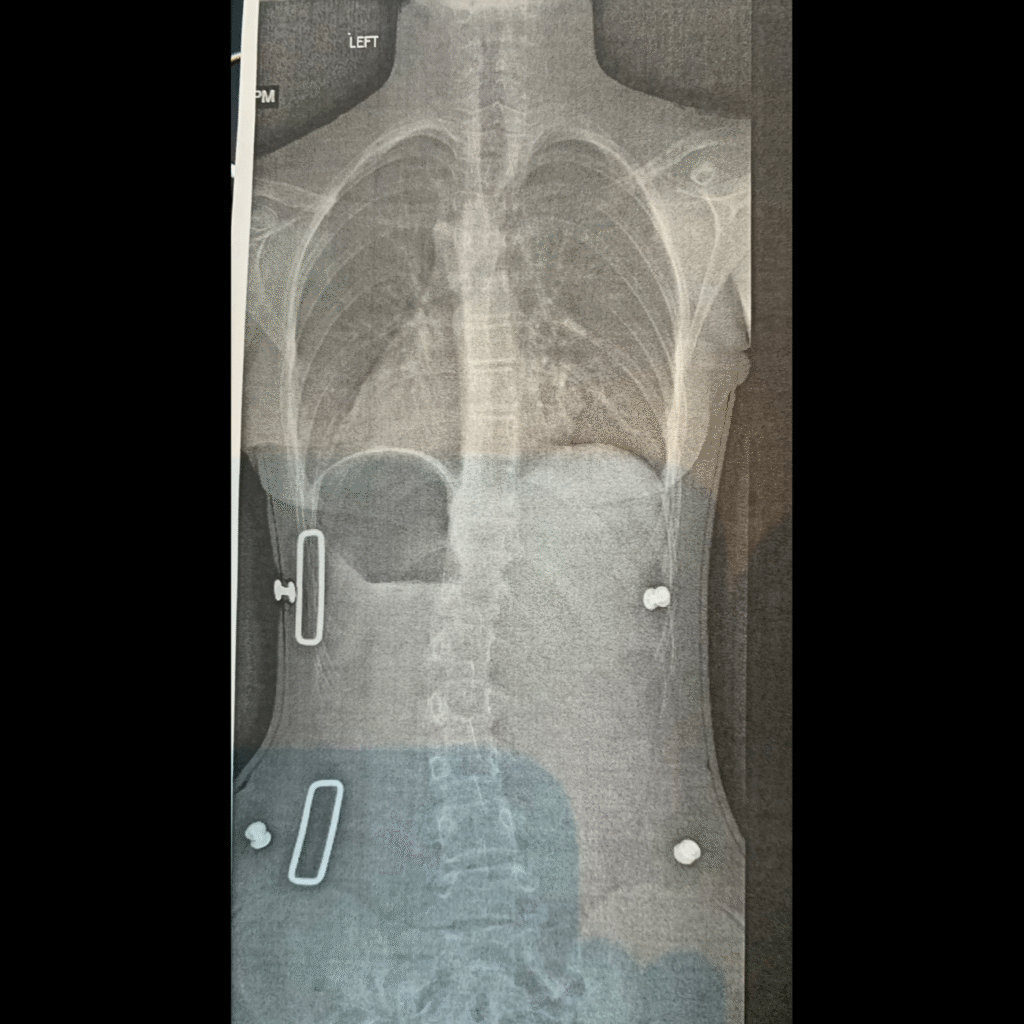

At the time I had no idea what Scoliosis was, or how it could be treated. I was completely shocked, my whole life was thrown upside down and I was confused by my own body. The unknown of Scoliosis freaked me out, and the idea of Spinal Cord Surgery freaked me out even more. Within the next couple of months I had started seeing an orthopedist, physical therapist, and an orthotist for a back brace. I did my physical therapy exercises in my basement with my dad every morning for 45 minutes before school for two years. All these mornings I was exhausted and drained from my schoolwork and sports practice. Although I was frustrated and tired, I knew this was an obstacle that I had to overcome. Wearing my back brace underneath my dress clothes to school everyday and sleeping with it at night was extremely uncomfortable physically and mentally. After wearing my brace for two years my doctor told me my curve decreased from 31 degrees to 28 degrees. I didn’t need surgery.